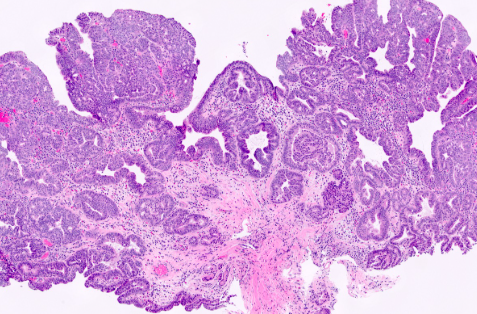

1. 위 선종이란 정확히 무엇인가?

위 선종은

위 점막 세포가 비정상적으로 증식해 생긴 ‘양성 종양’

입니다.

하지만 여기서 중요한 점은 단순한 혹(폴립)과 다르다는 것입니다. 위 선종은 세포 모양이 정상과 달라진 ‘이형성’ 단계입니다. 즉, 세포 구조가 변형된 상태로 암으로 발전할 가능성이 존재하는 병변입니다.

의학적으로는 다음처럼 구분됩니다.

- 저도 이형성 (Low-grade dysplasia)

- 고도 이형성 (High-grade dysplasia)

고도 이형성은 위암 직전 단계로 보는 경우도 있습니다.